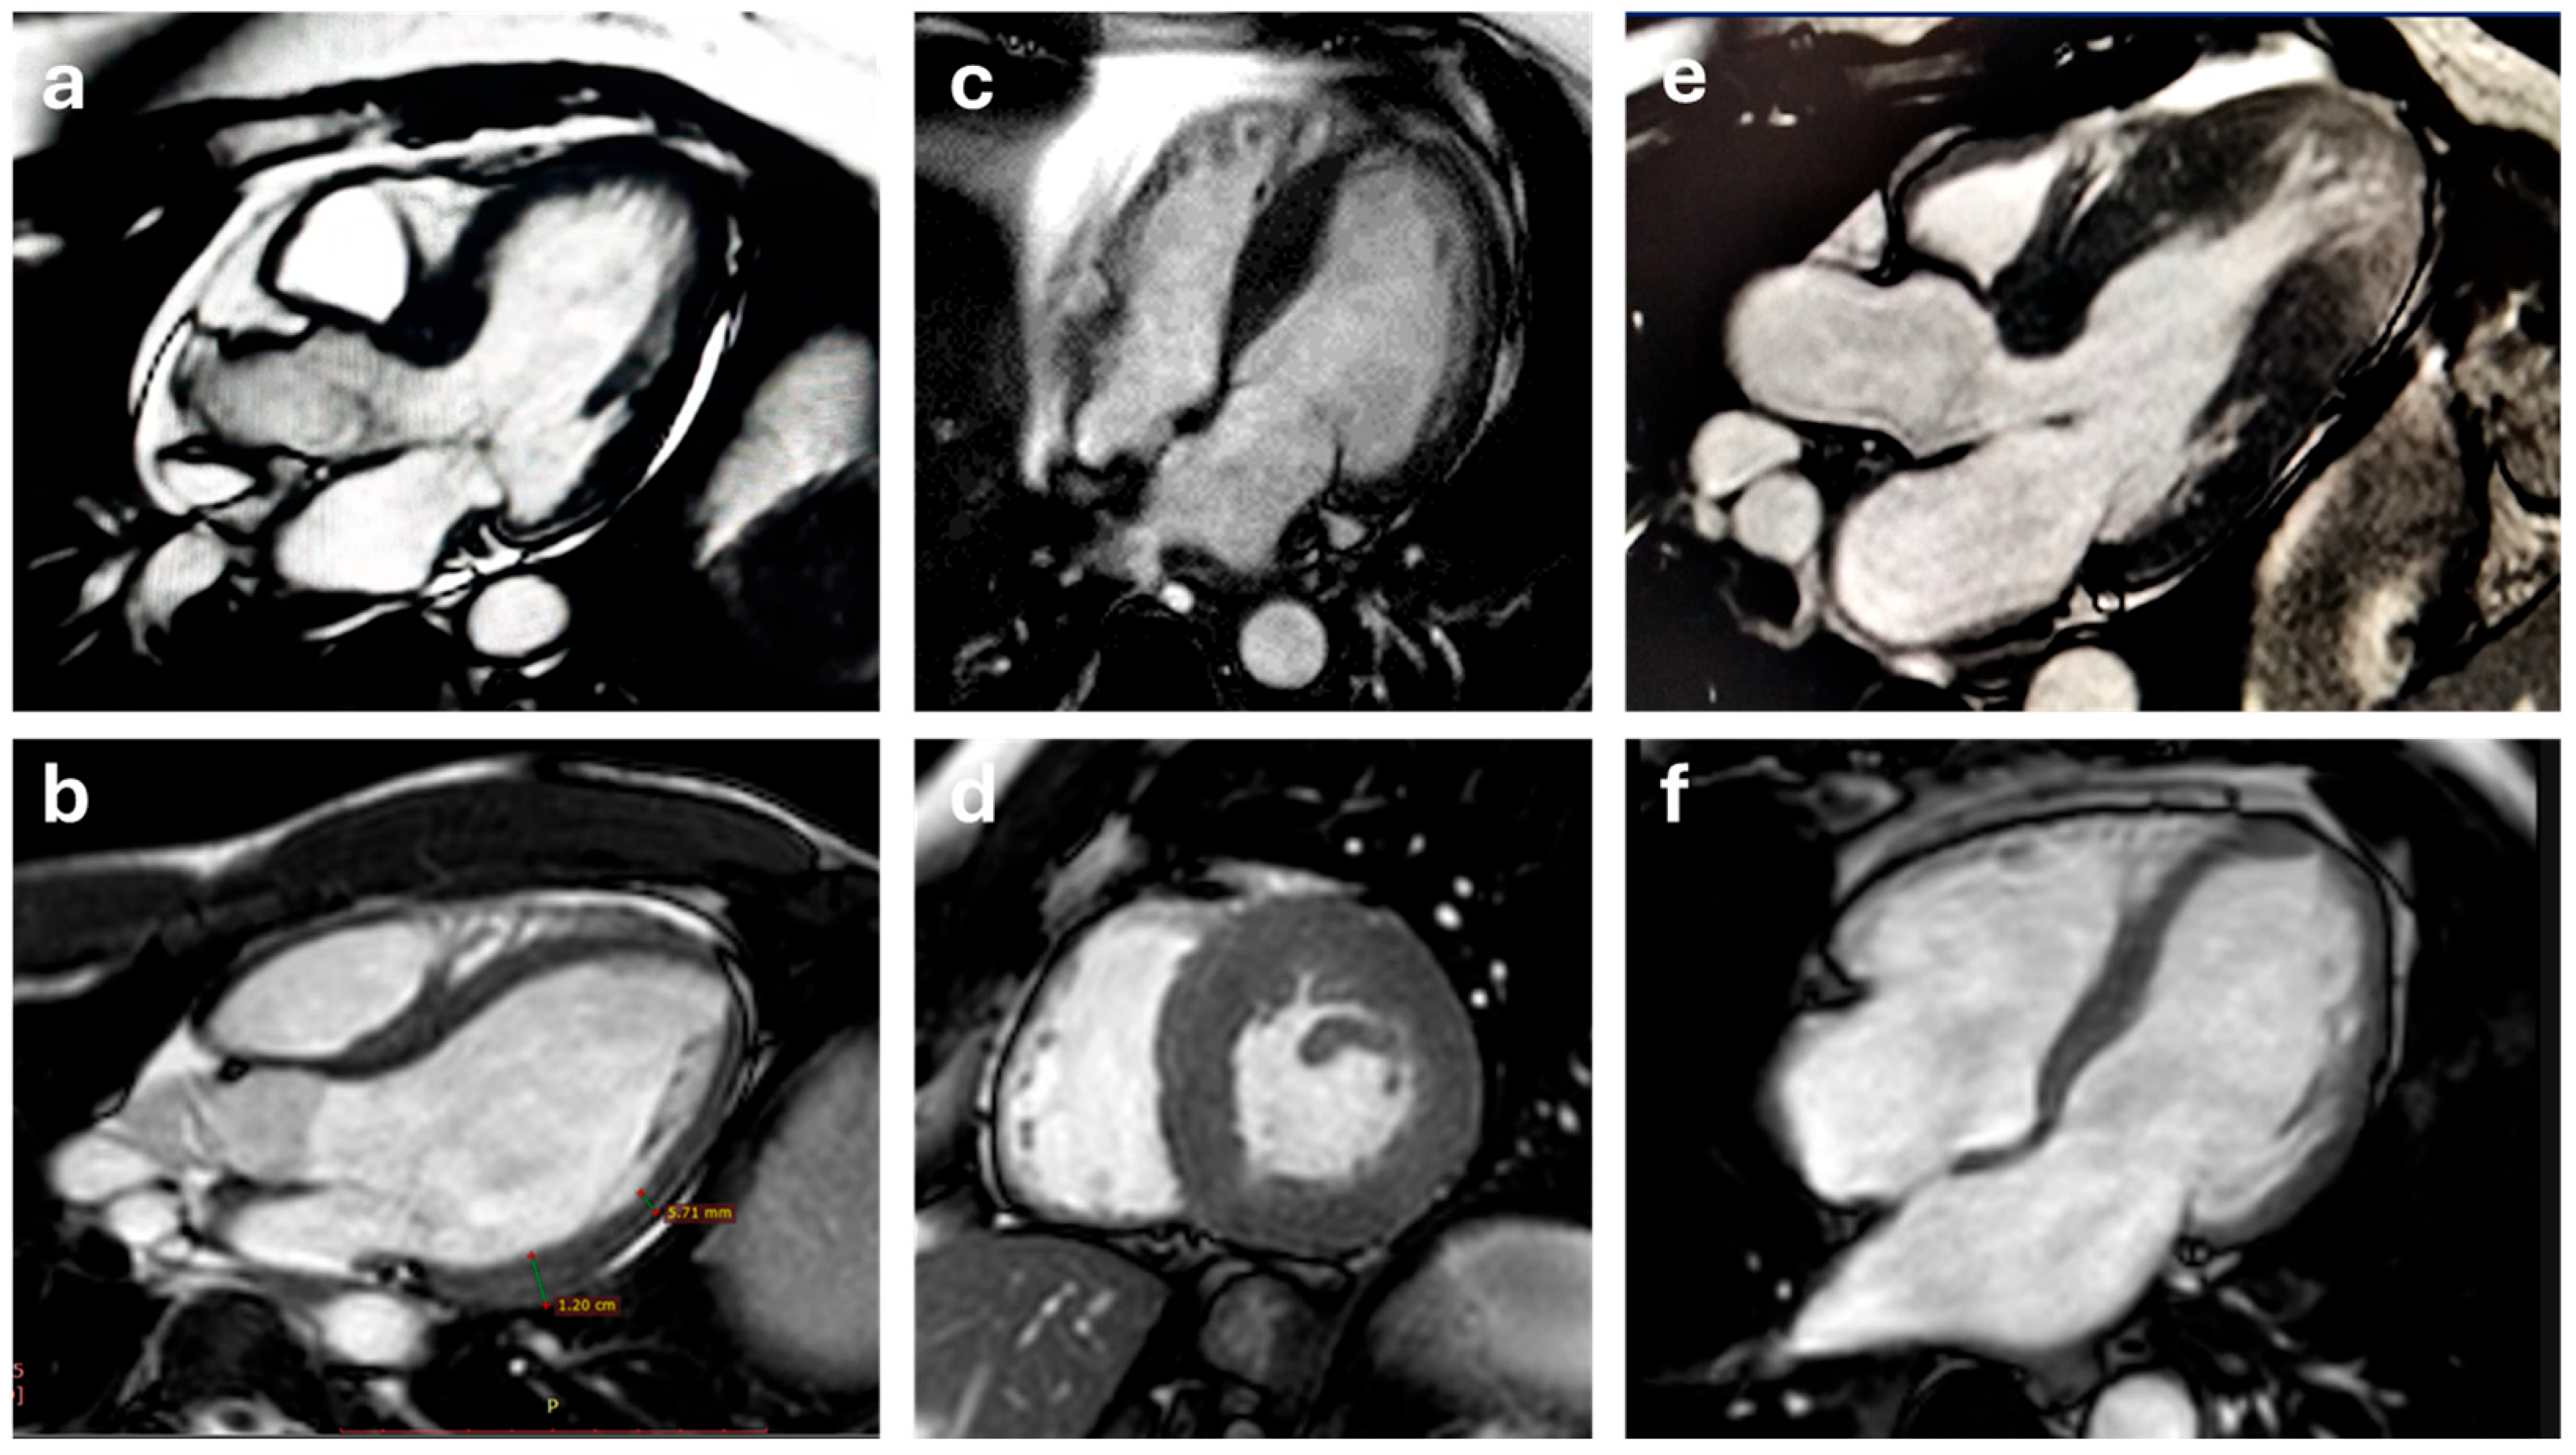

5.1. Cine-MR and Phase-Contrast Velocity Mapping Sequences

5.3. Late Gadolinium Enhancement